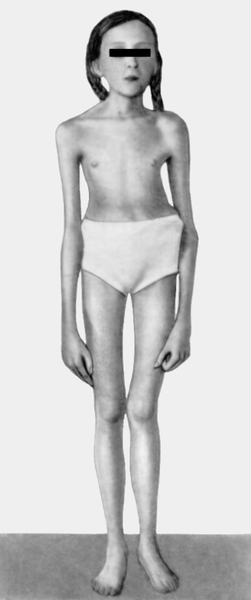

Neonatalnaya forma sindroma marfana klinicheskoe opisanie i kompleksnyj podhod k diagnostike i lecheniyu tema nauchnoj stati po klinicheskoj medicine chitajte besplatno tekst nauchno issledovatelskoj raboty v elektronnoj biblioteke kiberleninka (Тип файлу jpg)

Neonatalnaya Forma Sindroma Marfana Klinicheskoe Opisanie I Kompleksnyj Podhod K Diagnostike I Lecheniyu Tema Nauchnoj Stati Po Klinicheskoj Medicine Chitajte Besplatno Tekst Nauchno Issledovatelskoj Raboty V Elektronnoj Biblioteke Kiberleninka

Neonatalnaya forma sindroma marfana klinicheskoe opisanie i kompleksnyj podhod k diagnostike i lecheniyu tema nauchnoj stati po klinicheskoj medicine chitajte besplatno tekst nauchno issledovatelskoj raboty v elektronnoj biblioteke kiberleninka (Тип файлу jpg)

Neonatalnaya Forma Sindroma Marfana Klinicheskoe Opisanie I Kompleksnyj Podhod K Diagnostike I Lecheniyu Tema Nauchnoj Stati Po Klinicheskoj Medicine Chitajte Besplatno Tekst Nauchno Issledovatelskoj Raboty V Elektronnoj Biblioteke Kiberleninka